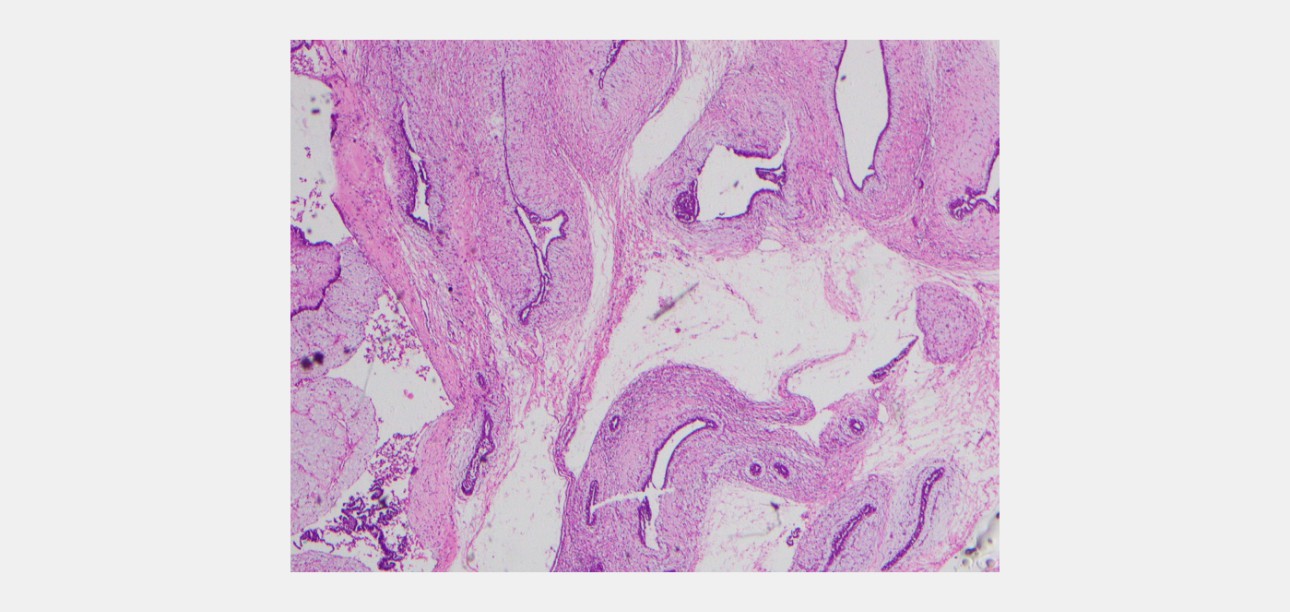

Histology Findings

6 core biopsies were taken. Sections reveal fibroadenoma composed of slit-like compressed glandular structures lined by a dual population of cells; surrounded by a myxoid stroma. There is no nuclear atypia or mitotic activity in the stroma. No evidence of DCIS or malignancy.